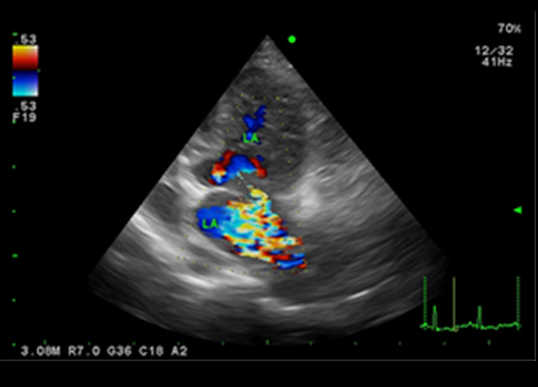

심장초음파(Echocardioagraphy) 검사

-

심장초음파를 통해 심장과 대혈관의 질환을 진단할 수 있는 검사법입니다. 심장초음파 검사는 심장 검사용 탐촉자를 이용하여 기본 영상과 도플러 검사를 통해 심장과 혈류의 움직임을 실시간으로 평가하고, 심근의 기능을 평가할 수 있는 검사입니다. 이를 통해 이첨판 폐쇄부전, 삼첨판 폐쇄부전, 동맥관 개존증(PDA), 폐고혈압과, 폐동맥 협착증, 대동맥 협착증과 같은 심장과 대혈관 질병을 진단하고 치료 경과의 확인을 위해 주기적인 재검사를 실시하고 있습니다.